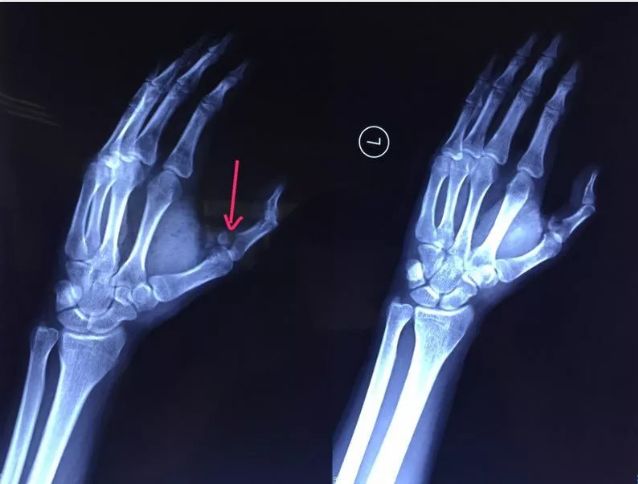

冰可乐竟把一男子手指炸成骨折

小袁发出惨叫,家人闻讯赶来,只见他左手动弹不得,伤口血流不止。他随即被送到湖南省人民医院就诊。X光检查发现,小袁左手拇指近节指骨骨折,需手术固定。当晚,医院为小袁进行手术,两小时手术顺利完成。术后,小袁的左手还需采用石膏固定4~6周。